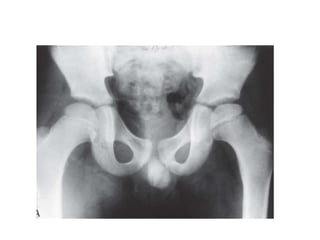

boy aged 9 years 7 months with Group B disease in the lateral pillar classification;

b: femoral varus osteotomy; c: outcome at 11 years of age.

boy aged 9years 7 months with Group B disease in the lateral pillar classification; b: femoral varus osteotomy; c: outcome at 11 years of age.